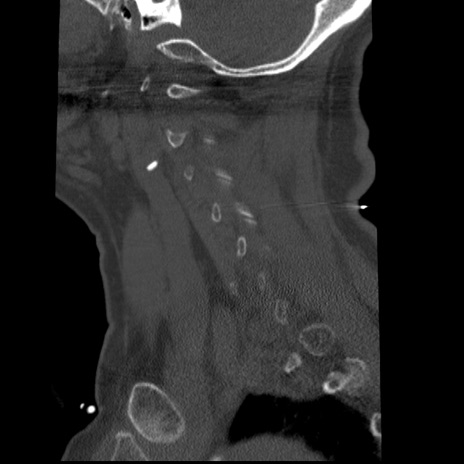

症例50 頚椎CT(矢状断像)

頚椎CT